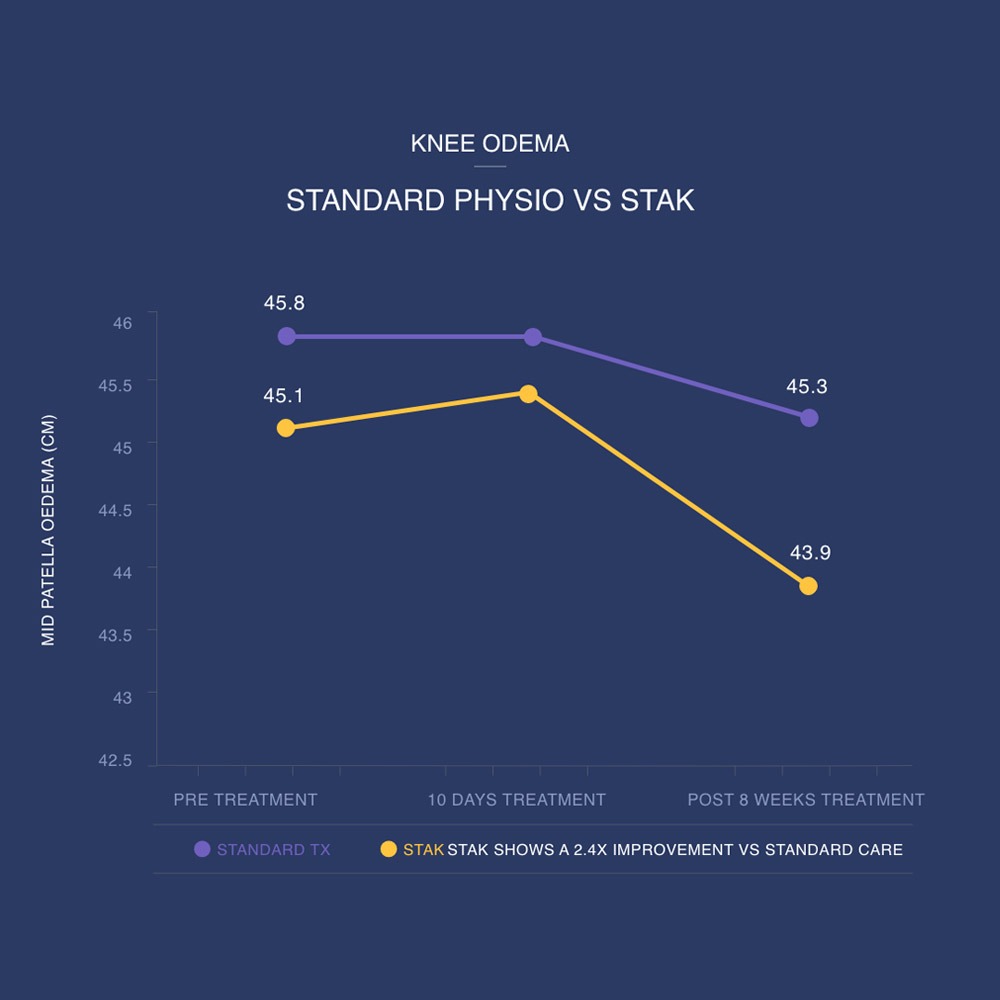

The STAK also demonstrates significant improvements in extension range and reduction in oedema. Experts believe the STAK high-intensity stretching programme is having a beneficial anti-inflammatory effect on the tissues.

In a clinical trial lasting 8 weeks, arthrofibrosis patients using the STAK gained on average 30 degrees range of movement compared to patients receiving standard physiotherapy who gained only 8 degrees.

Significantly more effective than the current Usual Care. The STAK Tool improved knee joint flexion by 30.4° vs to 7.7° for Usual Care over an 8-week intervention and maintained after 12-months.

"The STAK tool is an effective modality increasing ROM and reducing oedema, which can be used to offer home-based therapy to treat arthrofibrosis."